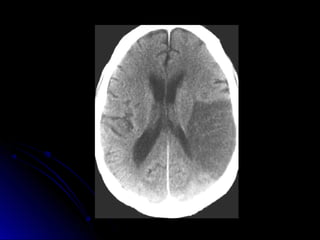

DIAGNOSTICO:DIAGNOSTICO:

TAC cerebral

RNM (utilidad técnicadedifusión y percusión)

Eco Doppler VasosCuello,

 Angio RNM, Arteriografía

Ubicación de las lesiones en TAC-RNM

DIAGNOSTICO:DIAGNOSTICO: Laboratorio. hemograma, glucemia,ionograma, ESD, tiempo deQuick, KPTT, orinacompleta Evaluación neurológica Radiologíatórax frente ECG y Evaluación Cardiológica, Eco bidi, Doppler TAC cerebral RNM (utilidad técnicadedifusión y percusión) Eco Doppler VasosCuello,  Angio RNM, Arteriografía

Ubicación de laslesiones en TAC-RNM